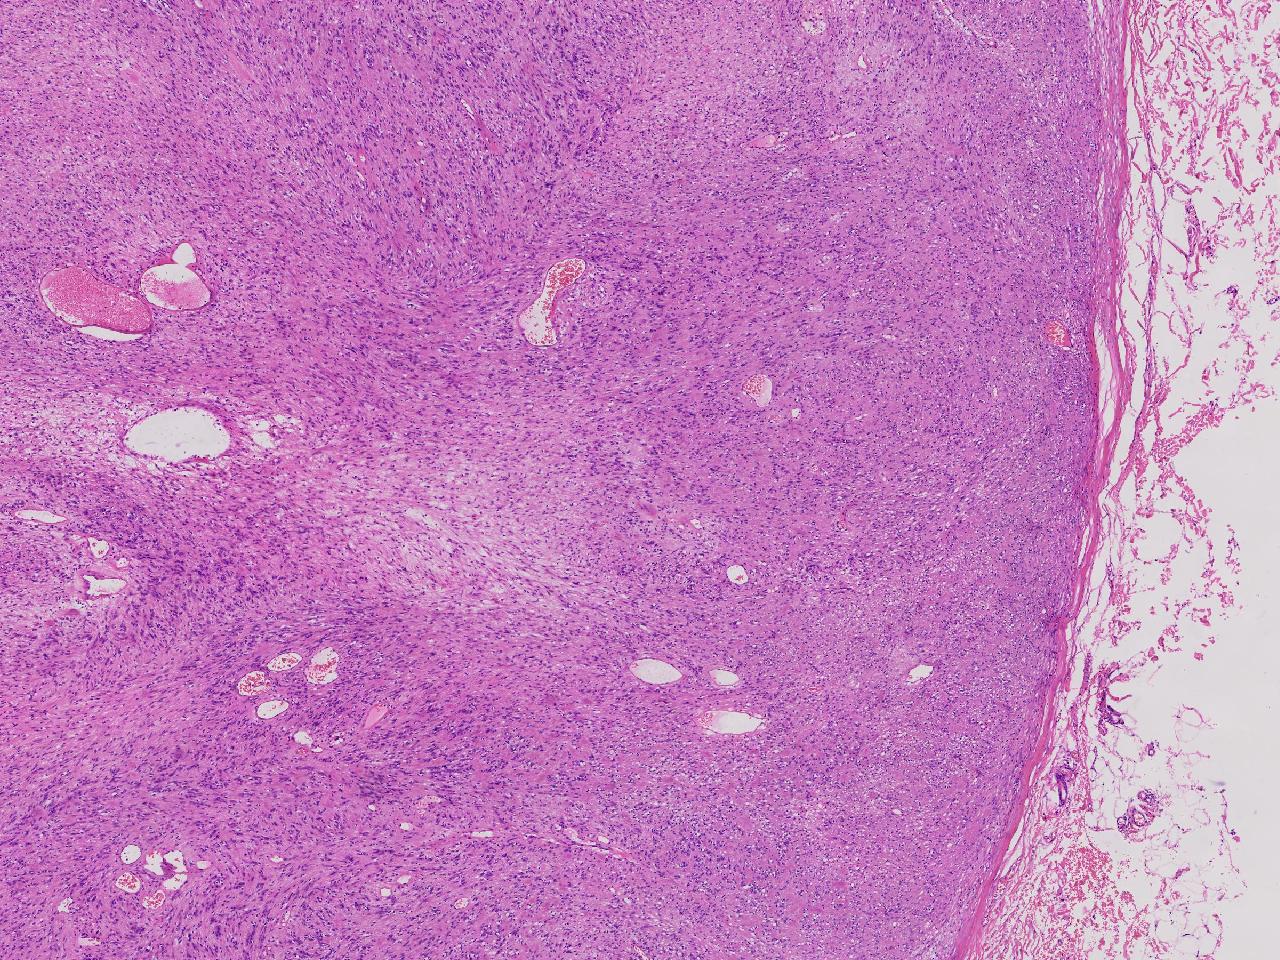

血管平滑肌瘤? 其他?

大体所见

卵圆形肿物一个,直径1.6厘米,上附皮肤。肿物切面灰黄实性,质中等。

考虑:结节性筋膜炎

完整的包膜。 首先还是考虑神经鞘。

神经鞘瘤。

建议除外平滑肌瘤,做IHC是更好的鉴别方式